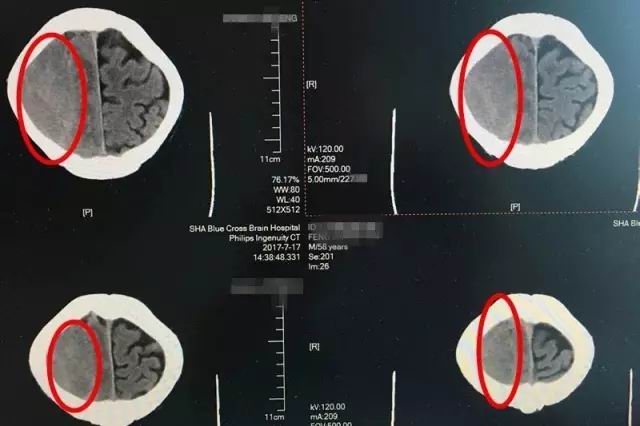

患者术前CT影像显示:红圈处为脑出血部位,出血量较大,颅内压升高

即便如此,时间不等人,等到七月中旬老冯一家辗转打听到上海蓝十字脑科医院,慕名找到神经内科的李振并主任时,老冯的症状已经开始加重了。入院时的脑CT影像检查显示,患者出血量增加,脑中线明显移位变质,左侧肢肌力3级(在和地心引力相反的方向中尚能完成其动作,但不能对抗外加的阻力),而且,他开始出现嗜睡、不思饮食的情况,如果再不及时治疗,患者很可能会陷入昏迷、偏瘫、失语、癫痫,巨大的风险正一步一步靠近。因此,迅速制定合理的治疗方案,才能及时挽救患者。